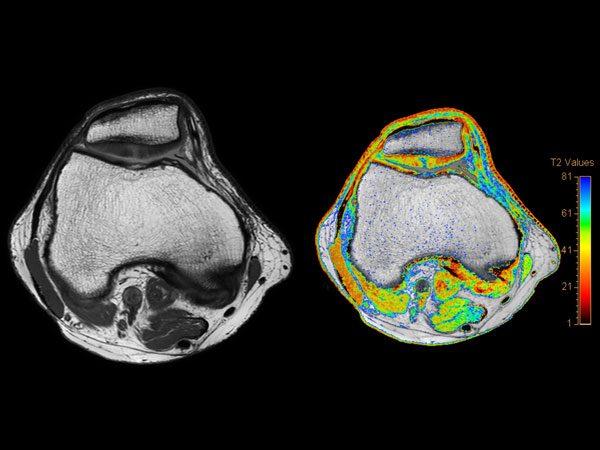

Knee Imaging with Cartilage Assessment

Middle aged board surfer presents with chronic knee pain. X-Ray shows no abnormalities. Follow-up MR examination requested.